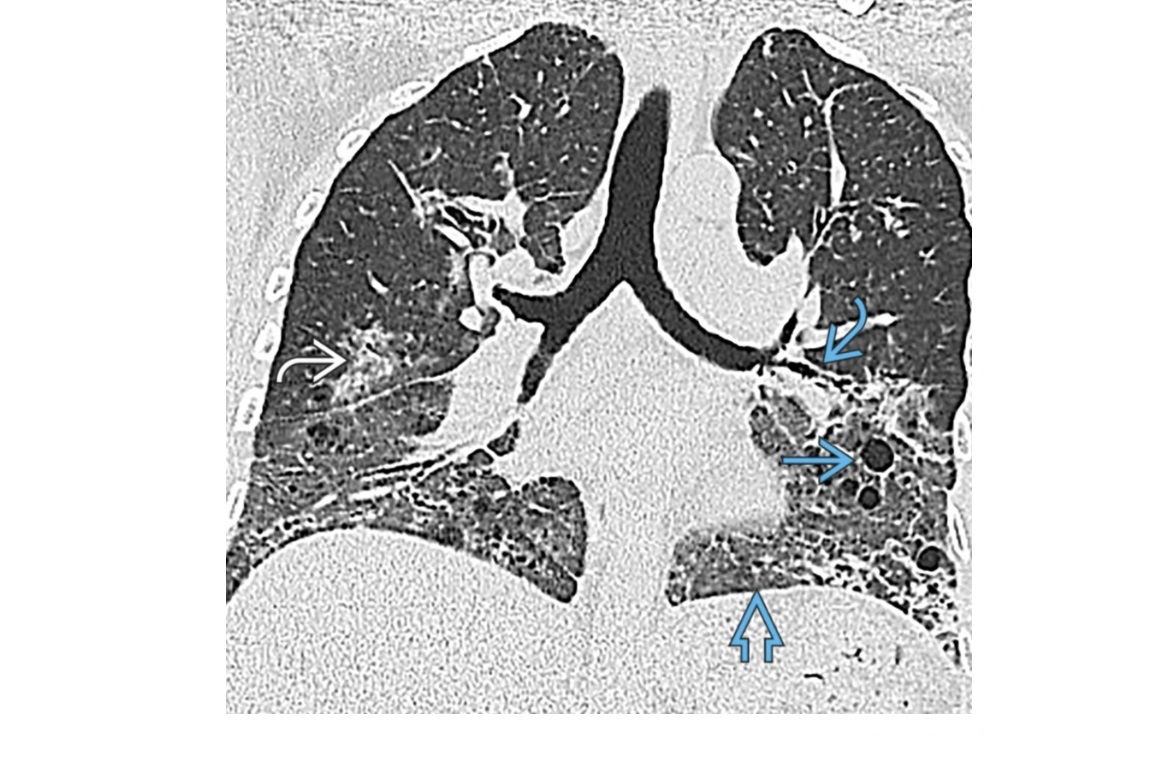

Lymphoid Interstitial Pneumonia - LIP

Basilar predominace

Thin walled cysts

GGO

Centilobualr micronodules

GGO clears with treatment

Associated with Sjogren’s

+ PCP, Hep B, EV

+ AIDs